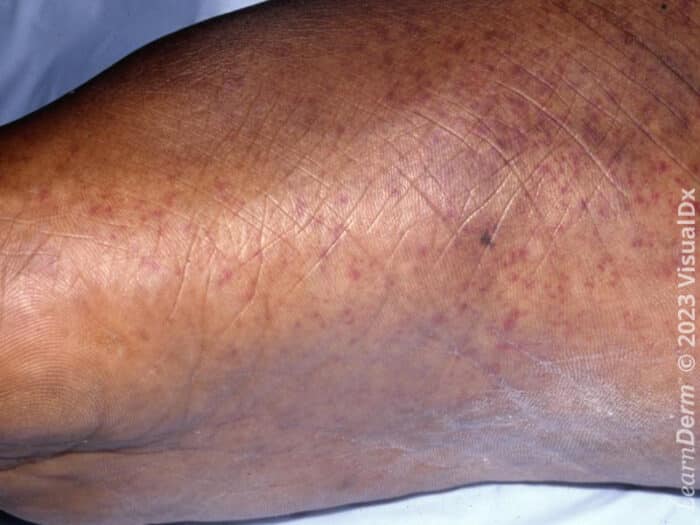

Finger Petechiae. Petechiae are tiny purple, red, or brown spots on the skin. Petechiae are red or purple dots on the skin that happen when blood vessels break under the skin's surface, creating a petechial rash. Overview covers definition, possible causes of this skin symptom caused by bleeding of tiny blood vessels. They may look like a rash on a person’s skin. Petechiae are tiny, flat patches that occur due to bleeding under the skin. They usually appear on your arms, legs, stomach, and buttocks. A petechial rash is caused by internal bleeding. Capillaries are the tiniest blood vessels that connect arteries. Stay the same color when you press your finger on them and then release; In children, petechiae most often appear on the arms, legs, stomach, and bottom. There are many possible reasons you may have petechiae, including viral and bacterial infections, use of. Petechiae are a sign of blood leaking from capillaries under your skin.

Capillaries are the tiniest blood vessels that connect arteries. Overview covers definition, possible causes of this skin symptom caused by bleeding of tiny blood vessels. They usually appear on your arms, legs, stomach, and buttocks. Petechiae are red or purple dots on the skin that happen when blood vessels break under the skin's surface, creating a petechial rash. Stay the same color when you press your finger on them and then release; Petechiae are a sign of blood leaking from capillaries under your skin. There are many possible reasons you may have petechiae, including viral and bacterial infections, use of. In children, petechiae most often appear on the arms, legs, stomach, and bottom. They may look like a rash on a person’s skin. A petechial rash is caused by internal bleeding.